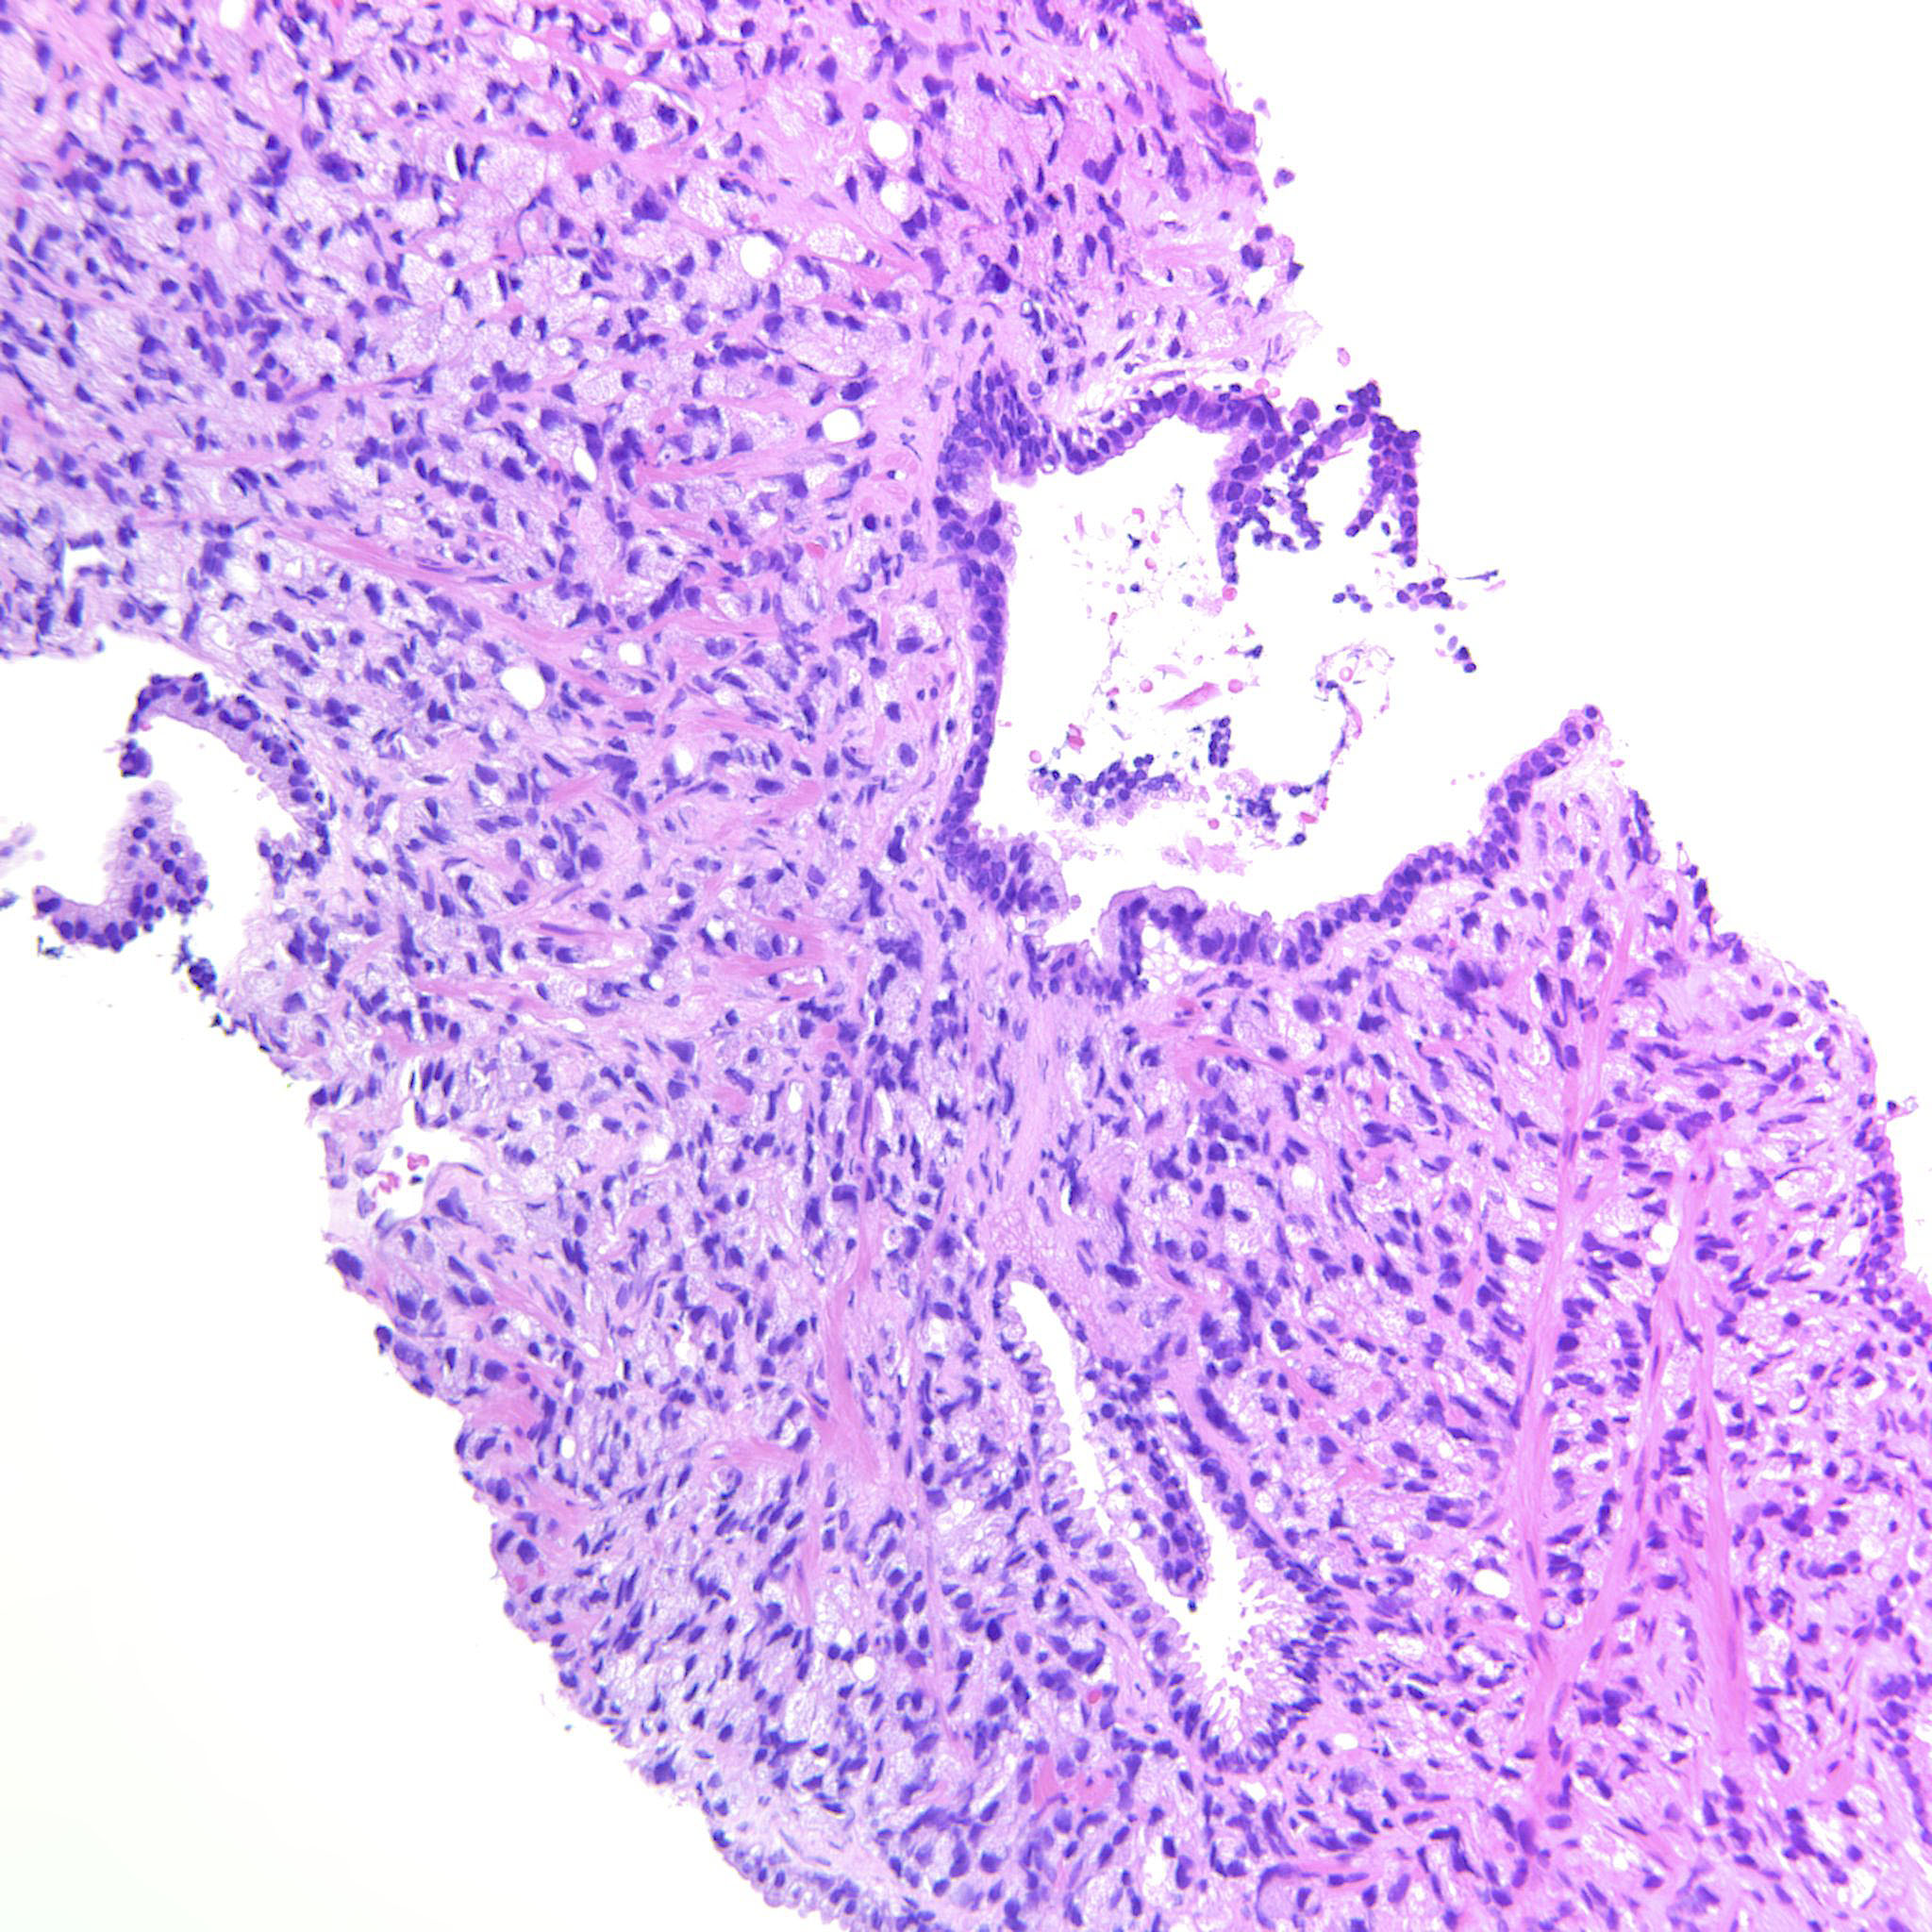

Consensus grade: GS 9-10 (ISUP 5)

Case description (by case creator):

Large sheets of fused glands but also sheets of tightly packed pale single cells.